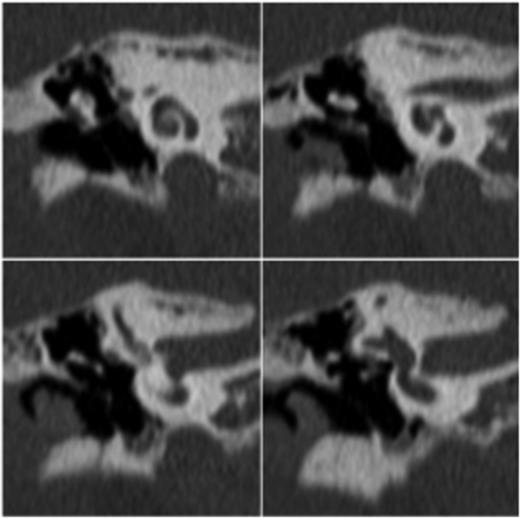

At this stage, a computed tomography (CT) scan of the temporal bone was undertaken. The stapes was maloriented on the oval window; however, the other ossicles appeared normal (see Figs 1 and 2). There was no middle ear effusion at the time of the CT scan.

Transverse high-resolution CT demonstrates intact ossicles with malposition of the stapes